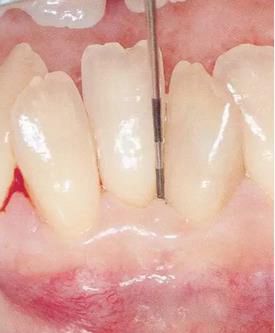

▲圖1

牙位異常例①。由于牙列擁擠造成牙根接近。